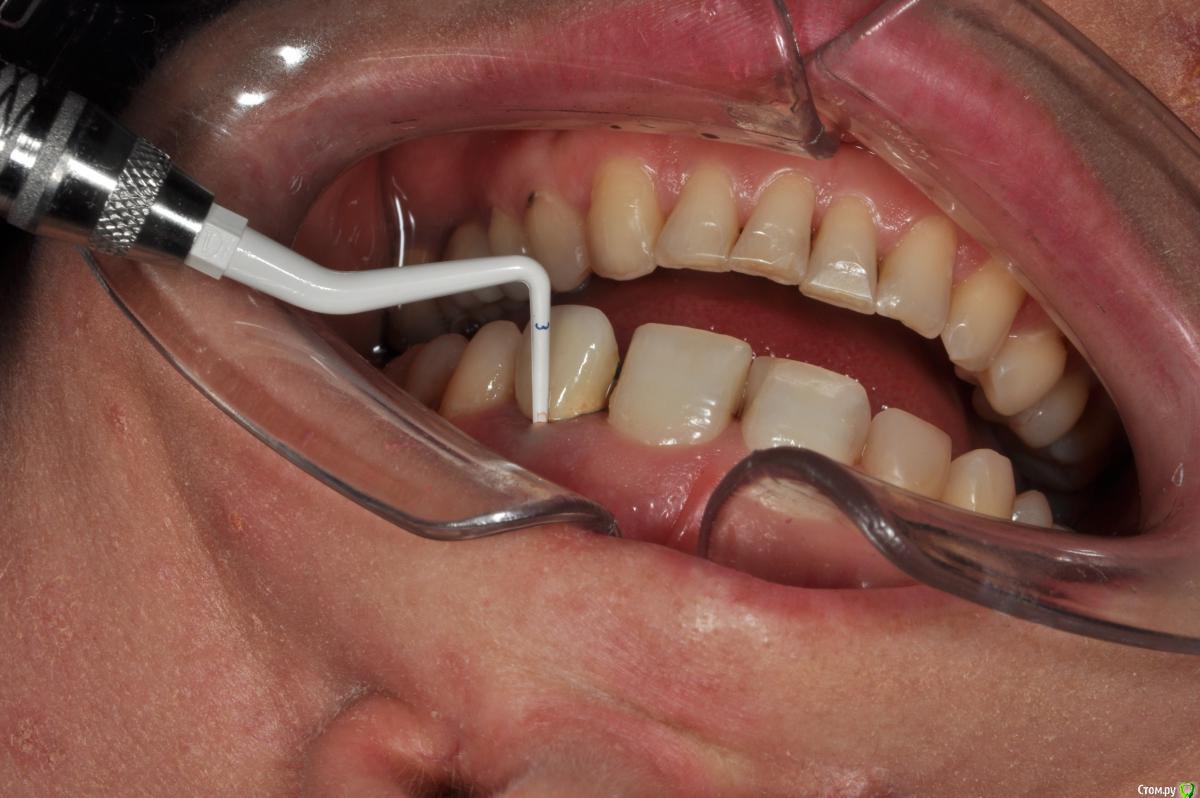

Пациентка 37 лет, не курит, соматически здорова. Частое выпадение ЛШКВ с коронкой. Диагностирована  фрактура вестибулярной стенки кореня зуба 22. Линия улыбки высокая. Биотип толстый.  Отсутствие вестибулярной пластинки, карман 8мм без ексудата.  Латеротрузия через 22.